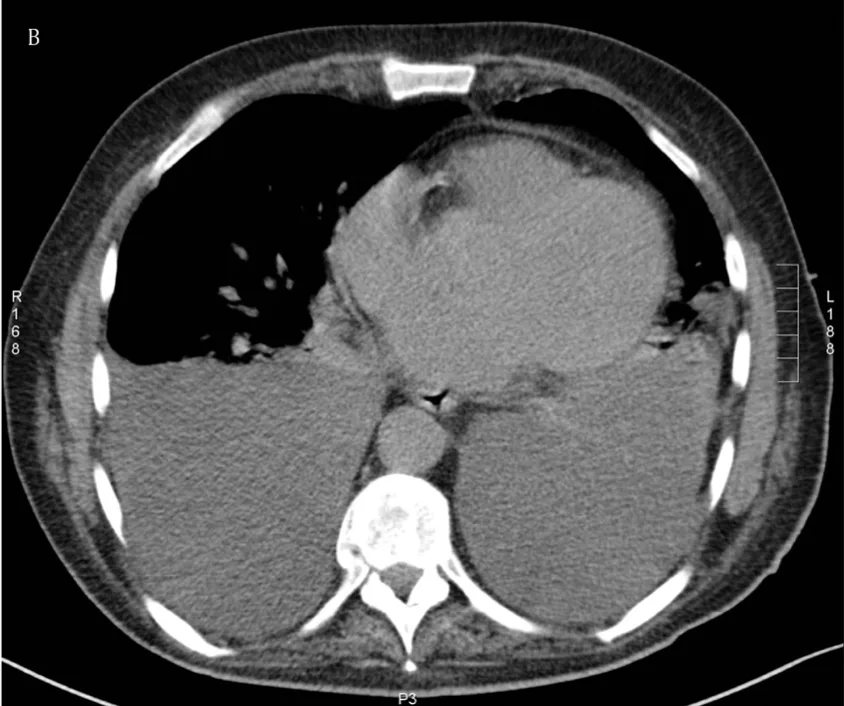

本来は, 空気が入っていて, 黒く写る肺の背中側(画面の下側)に灰色に写る水(胸水)が貯まっており, それによって肺が半分ほどしか写らなくなっています.

胸部CTでは, 両側に大量の胸水が貯まっていました.